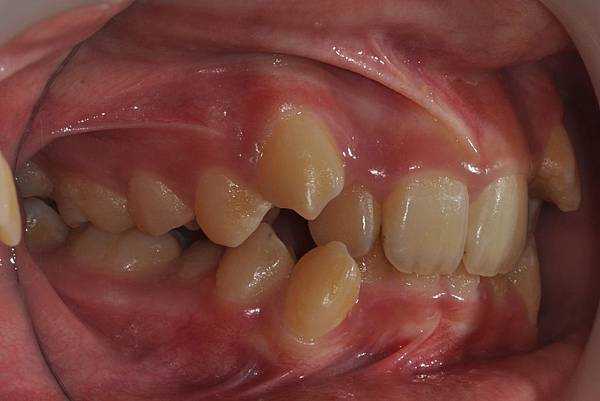

拔牙改善高位虎牙

虎牙妹的女神蛻變之旅~

此案例因為空間不足排列牙齒,

考量到不拔牙將使得牙齒前凸破壞患者原本和諧的側臉。

故上下左右各拔一小臼齒。